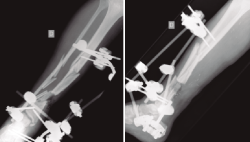

Figura 3. Rescate de la fractura mediante fijador externo de tipo Ilizarov, empleado como tratamiento puente antes del tratamiento definitivo.

Figura 4. Una vez confirmada la erradicación de la infección, se procedió a la retirada del fijador externo. Se realizó un aporte de injerto óseo autólogo procedente de la tabla interna de la tibia y una posterior fijación interna de la fractura mediante una artrodesis de tobillo. El resultado final fue una correcta consolidación de la fractura.